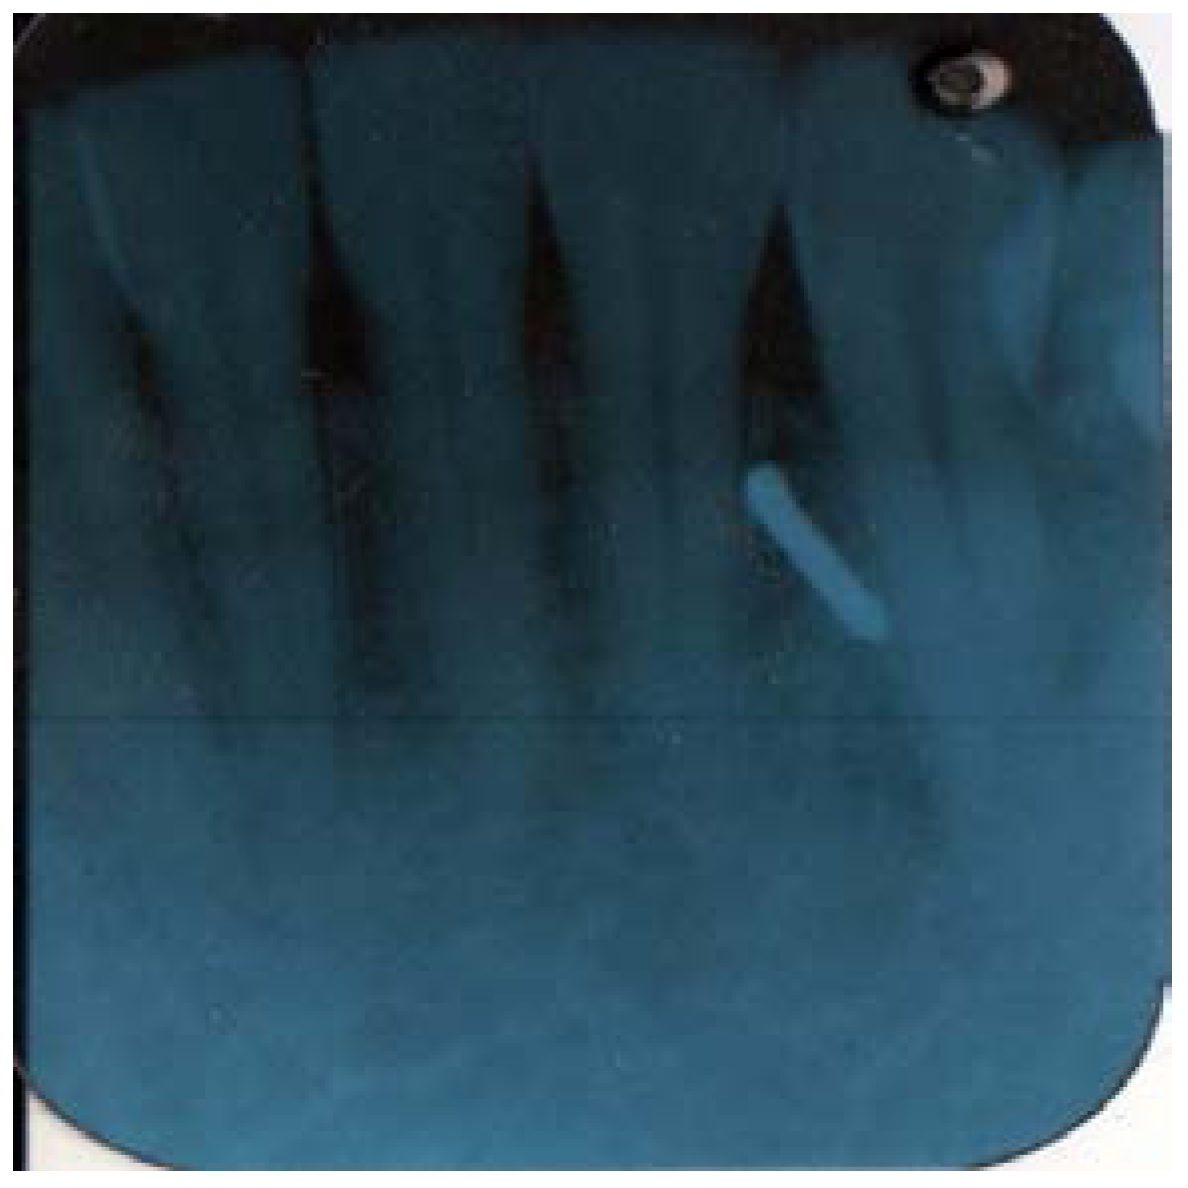

Later in the day, the dentist felt a slight hardness and slight pain upon palpitating the area. By the next day, the swelling had progressed slightly and the dentist felt a slight pain upon palpitation or any movement, such as chewing Figure 1 and Figure 2. He did not think that the small piece of bur was lodged in his chin. A decision was made to have radiographs taken, which included a panoramic and a peri-apical radiograph. Subsequent review of the radiographs revealed a radiopaque image consistent with a broken piece of the bur in the soft tissue of his chin, in the vestibule of the mandibular anterior left side Figure 3 and Figure 4.

Figure 3.

Panoramic X-ray.

Figure 4.

Pri-apical X-ray.